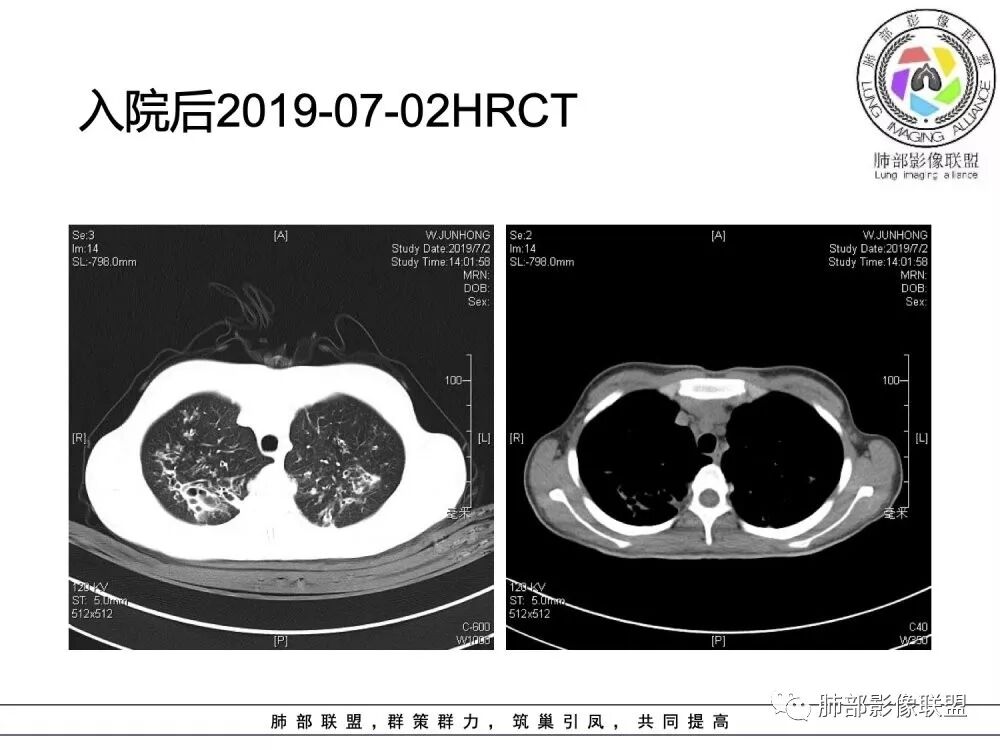

胸部CT检查:

(1)支气管壁增厚、支气管扩张

可广泛分布于两肺各叶,尤其是两肺上叶多见。支气管扩张主要是轻、中度柱状支气管扩张。支气管壁增厚既可发生于扩张的支气管,也可发生于非扩张的支气管,常为轻度增厚,管壁内外比较光滑。

(2)两肺弥漫性肺气肿

表现为肺野密度低而不均,在不同病例病变程度轻重不一,婴儿或儿童患者多见。

(3)支气管黏液栓

由于黏液分泌物潴留在气管内形成,依据黏液存留的支气管走向不同而形态各异,多呈圆形、椭圆形、管状或尖端指向肺门的“V”形或“Y”形高密度阴影,密度均匀,边缘光滑锐利,CT值一般为15±10HU,但存留较久的黏液栓CT值可高达40~80HU,增强扫描无强化。

(4)薄壁含气囊腔

因支气管扩张、气肿性肺大泡及间质性气囊肿形成大小不一之囊腔,与支气管相关。

(5)斑片状阴影

表现为感染性支气管肺炎和亚段肺不张。呈1~3cm大小不等的斑片状高密度影,上肺野常见或上肺野病灶分布较多。